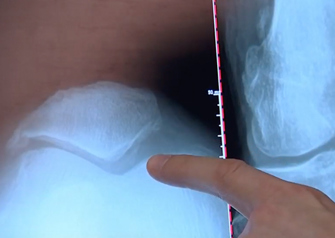

Amniotic fluid might now be used to alleviate knee pain in patients suffering from osteoarthritis, according to doctors at Midwest Orthopaedics at Rush. NBC 5 Chicago's Lauren Petty sat down with Dr. Adam Yanke to learn more about how amniotic fluid can be used to help certain patients who have knee arthritis that might not be severe enough for knee replacement surgery.